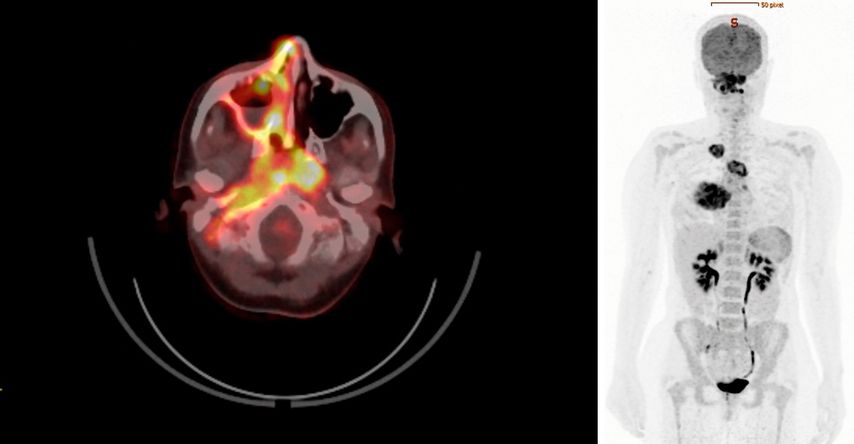

Zur weiteren Stadieneinteilung wurde ein 18F-FDG-PET/CT durchgeführt. Dieses wies eine hohe metabolische Aktivität auf – nicht nur in den pulmonalen Veränderungen, sondern auch im Bereich des raumfordernden Pseudotumors an der gesamten rechten Schädelbasis sowie in weiteren multifokalen Läsionen im Sinne eines generalisierten Stadiums mit Multiorganbefall (Abb.1).

Abb. 1: 18F-FDG-PET/CT mit hoher multifokaler metabolischer Aktivität bei Vaskulitis mit Multiorganbefall (Quelle: Universitätsklinik für Nuklearmedizin Innsbruck)